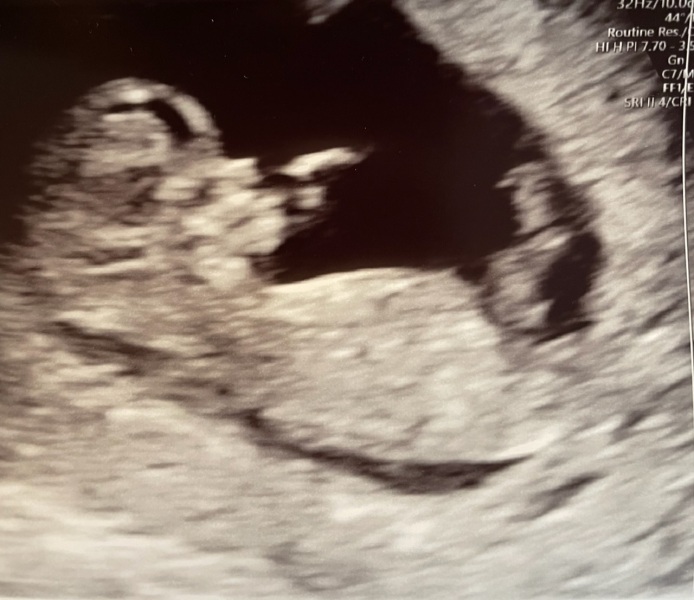

@Abbi95 thats a beautiful photo!

Thanks everyone. It went perfect! ❤️

gg9320 · 21/12/2022 15:08

Yay so lovely to hear the 12 week scans went well today! The blobs have grown into babies!! I have mine next week, feels forever away 😂